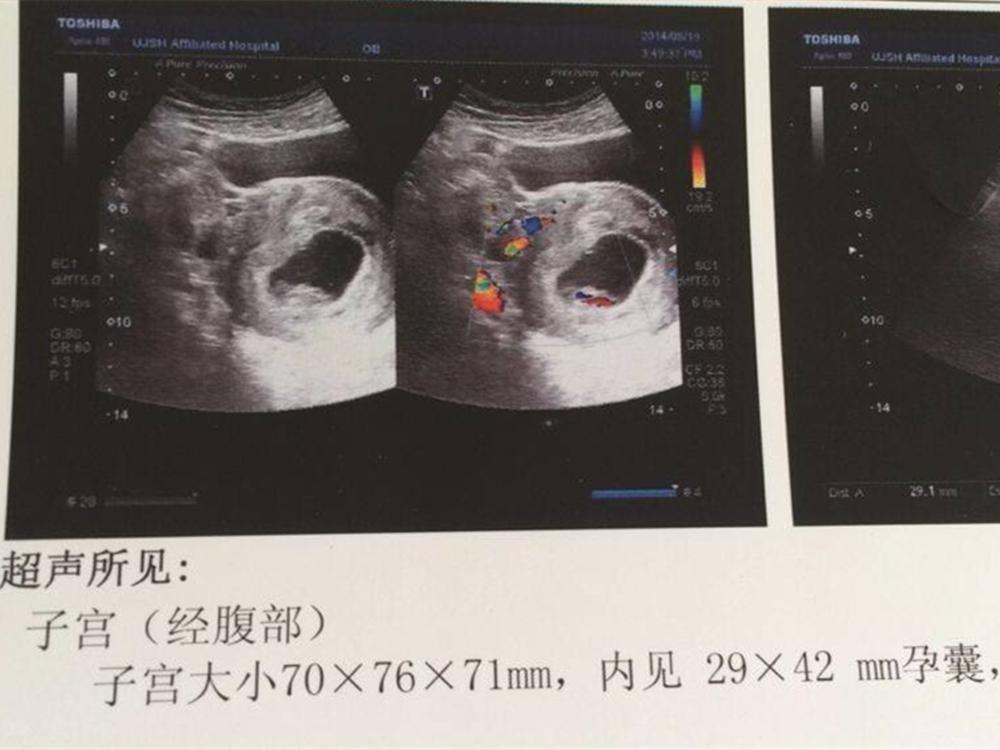

一. 胚囊:

对大部分月经规律的孕妇来说,停经在五周左右时就能看到胚囊了。

而且,随着停经的时间越来越长,胚囊的形状和尺寸也会发生较大程度上的变化。停经五周后再过几天,胚囊内部还会有一种叫做“卵黄囊”的物质。

不过,有时当宫腔出现积液,可能也会造成出现胚囊的错觉,这种情况也叫做“假胚囊”。

可一旦检查发现“卵黄囊”,几乎就可以完全确定这就是胚囊了。